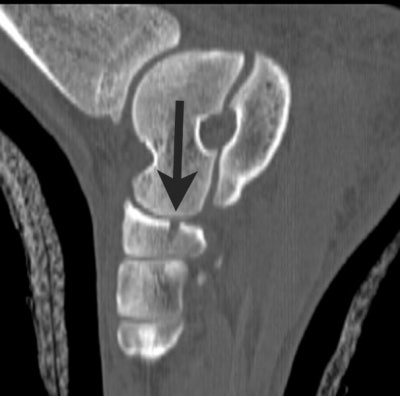

![]() |

| Sagittal reformatted image through the lateral aspect of the foot shows inferior subluxation of the cuboid (arrow) relative to the fourth metatarsal. |